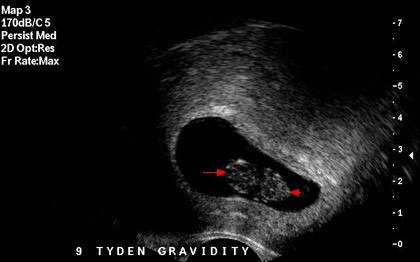

Badanie u pani ginekolog wszystko potwierdziło, a ja tylko się śmiałam z tego, że zaczęłam się złościć na zatrzymanie moich procesów kobiecych :D. 9. tydzień ciąży.